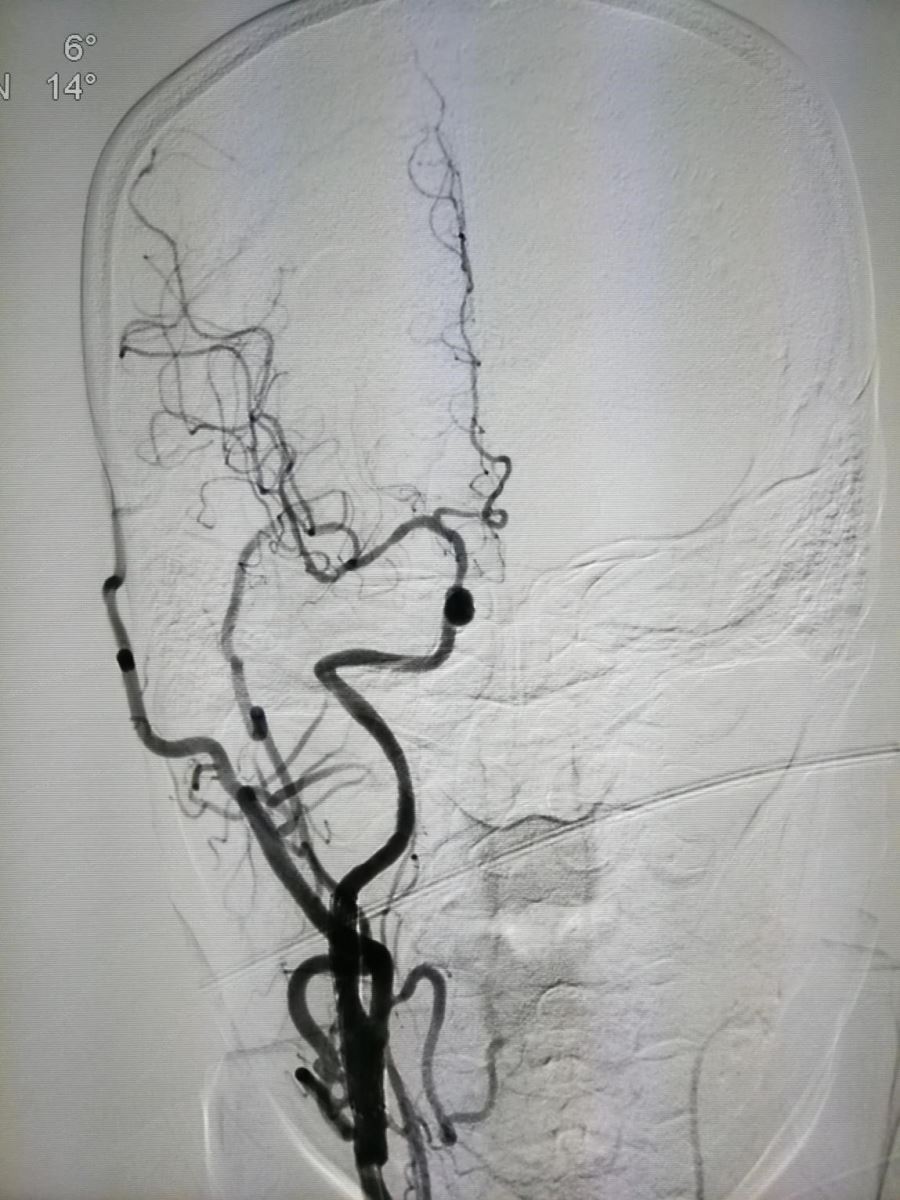

头颅CT、头颅MRI、MRA(磁共振颅内动脉血管成像)已广泛应用于临床,对脑血管病的定位、定性诊断帮助极大,但是并不是所有脑梗死患者的病变原因都在颅内。缺血性卒中发病原因的Toast分型,第一项即为大动脉粥样硬化性病变引起的卒中,因此应引起重视。如图1:

.jpg)

图1

如果单看颅内血管成像,无需介入治疗,但如果连同颈部动脉血管成像(图2、3)。